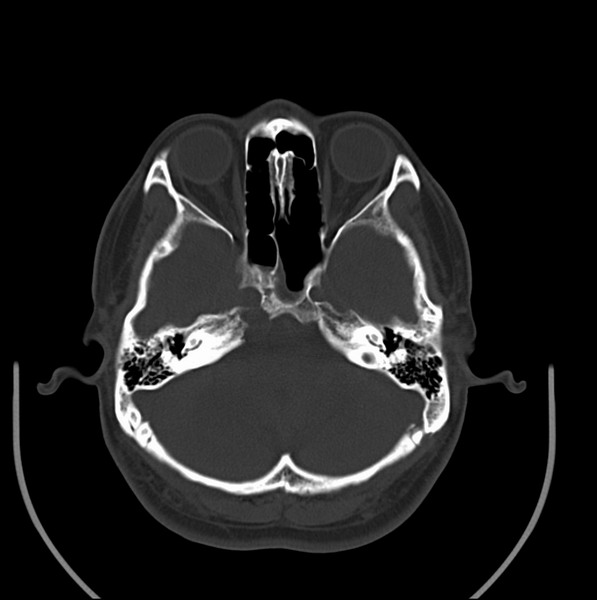

男、30、发现鼻咽部肿瘤侵犯海绵窦,未发现明显淋巴肿。请问国内那家医院治疗鼻咽部肿瘤最好?手术以何种方式为主?病灶可否全部切除?急切期待的大家的帮助。

扫描示鼻咽腔不对称,中度狭窄,右侧咽隐窝消失,局部软组织肿块,鼻咽右侧壁增厚形成肿块,突入鼻咽腔,肿块平扫呈等密度,肿块向深部侵润,右侧翼内外肌受侵,右侧咽旁间隙变窄;向后生长,头长肌界线欠清,向后上生长侵犯同侧颈动脉鞘区。双侧海绵窦增宽,内见软组织影与鼻咽部肿块相连。考虑鼻咽癌。鼻咽癌主要是放射治疗,且效果较好;到当地有治疗设备较大医院治疗即可。

这个病例有点特殊,和常见的鼻咽癌不太一样,以向颅内侵犯为主,骨质破坏区小。鼻咽癌首先要考虑,有没有其他可能?本人不会看mr片,期待有人能讲解,期待病理。

鼻咽部新生物(纤维血管瘤?鼻咽癌?)侵犯右侧中颅窝底及右侧海绵窦;建议必要时活检定性。

鼻咽部新生物侵犯右侧中颅窝底及右侧海绵窦,鼻咽癌可能性大。建议增强扫描。纤维血管瘤禁忌穿刺。

典型鼻咽癌侵犯右侧海绵窦(对放疗敏感)